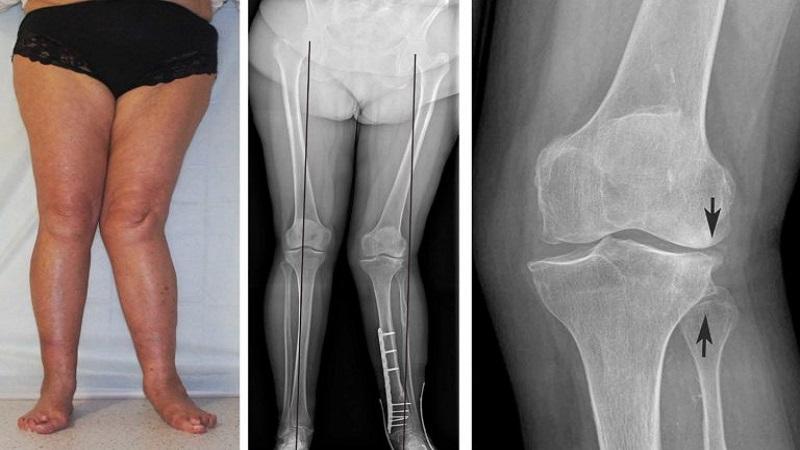

- деформация конечности. Без должного лечения происходит постепенное истощение гиалинового хряща, который выполняет амортизирующие и двигательные функции суставов, связки начинают окостеневать. В результате колено увеличивается в объеме и приобретает неровный, бугристый вид.

Пальпация помогает выявить плотные образования вдоль суставной щели, уплотнение суставной капсулы, а также хруст в суставе при движении, синовит и повышение температуры кожи. Также исследуются движения в пораженном суставе. Объем обследований для каждого пациента определяется индивидуально, при этом рекомендуется использовать методы, которые наиболее информативны для решения конкретной диагностической задачи.

- Рентгенография. Это основной метод диагностики гонартроза, хотя на начальной стадии он может не показать патологию. На второй стадии можно увидеть остеофиты, участки окостенения и сужение суставной щели.